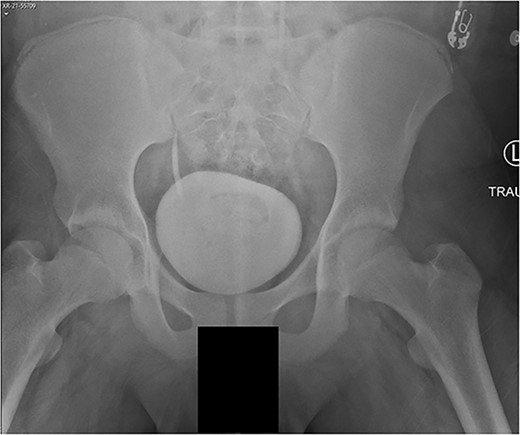

The patient tolerated the procedure well and recovered uneventfully. He was noted to have circumferential osseous healing at 1 year and underwent bilateral femur IMN removal 1.5 years postoperative without complication (Figs 4a–d and 5a–d).

(a) Right femur AP radiograph. (b) Right femur lateral radiograph. (c) Left femur AP radiograph. (d) Left femur lateral radiograph.